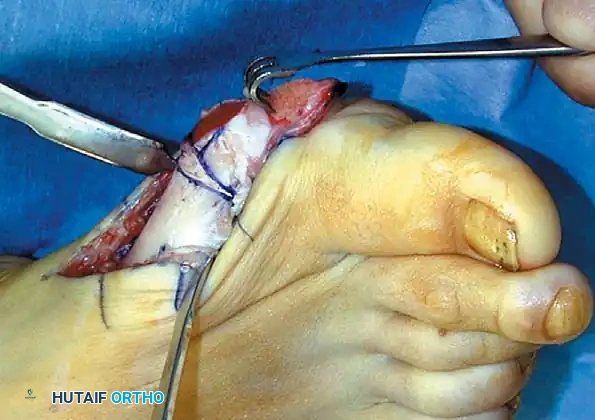

REMOVAL OF THE FIBULAR SESAMOID

• When the medial eminence and phalangeal base have been excised, remove the fi bular sesamoid.

• Place a sturdy two-toothed retractor beneath the metatarsal head, and have an assistant lift it dorsally.

• Using a Freer elevator or a small osteotome for its strength, mobilize the fi bular sesamoid (Fig. 78-31A to C). This may be diffi cult in elderly patients with signifi cant deformity and adherence of the sesamoid to the metatarsal head. Lift the metatarsal dorsally for exposure (Fig. 78-31D and E).

• Pull the plantar medial capsule medially. This requires a fi rm grasp on the capsule. The medial traction brings the intersesamoid “ligament” into better view.

• Incise the intersesamoid ligament longitudinally with a No. 67 Beaver or No. 15 Bard-Parker blade. If tenotomy scissors are used, place one arm of the scissors under the ligament (this arm rests on the dorsal side of the fl exor hallucis longus) and the other arm dorsal to the ligament.

• When the intersesamoid ligament is incised, grasp the sesamoid fi rmly with forceps or a small Kocher clamp, fl ex the toe at the interphalangeal and metatarsophalangeal joints to relax the fl exor hallucis longus tendon, and pull the fi bular sesamoid distally and medially.

• With release of the intersesamoid ligament, the medial surface of the fi bular sesamoid is free from soft tissue. Distally, the sesamoid is free because of resection of the base of the proximal phalanx. This leaves two sides of the sesamoid, distal and medial, free of soft tissue.

• While pulling the sesamoid distally and medially, use a small blade to incise along the lateral margin of the sesamoid under direct vision. Keep pulling the head of the metatarsal dorsally and holding the hallux distracted and in fl exion. This greatly aids in identifi cation of the margins of the fi bular sesamoid, particularly laterally and proximally.

• The most diffi cult part of the sesamoidectomy and that which should be done last is release of the proximal lateral corner of the sesamoid where the fl exor hallucis brevis lateral head inserts. While incising the lateral capsular attachments to the sesamoid, do not bury the blade of the knife because the neurovascular bundle to the lateral side of the hallux is just lateral to the capsule.

• Now all attachments to the fi bular sesamoid have been removed except the lateral head of the fl exor hallucis brevis, which inserts on the proximal lateral margin of the sesamoid. This is a diffi cult section to remove; however, this section can be released under direct vision by pulling the sesamoid distally and medially and lifting the metatarsal head dorsally with a strong two-toothed retractor.

Fig. 78-31 Excision of fi bular sesamoid in modifi ed Keller procedure. With base of proximal phalanx removed and medial eminence excision, exposure of fi bular sesamoid is not as diffi cult from medial incision. A, Operative photograph showing elevation of fi rst metatarsal with strong two-tooth retractor and use of small osteotome to mobilize fi bular sesamoid and lateral capsuloligamentous (frequently contracted) structures. Osteotome is between metatarsal head and lateral sesamoid. When mobilization of fi bular sesamoid is complete, entire sesamoid is visible for excision. Note chondromalacia of tibial sesamoid articular surface medial to osteotome. B, Fibular sesamoid has been excised, and lateral capsular structures and conjoined tendon (in forceps) have been released. Neurovascular bundle to lateral side of hallux is adjacent to these structures. C, Diagrammatic representation of modifi ed Keller procedure. By excising fi bular sesamoid, valgus moment of conjoined tendon of fl exor hallucis brevis and adductor hallucis no longer pulls fl exor hallucis longus tendon laterally (carrying hallux with it) through capsulosesamoid plantar plate and pulley system. D, Metatarsal head must be lifted dorsally to excise fi bular sesamoid under direct vision. E, Note exposure of fi bular sesamoid after mobilization of metatarsal head. Continued